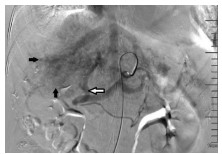

Incidence rates of hyperamylasemia and acute pancreatitis after percutaneous transhepatic biliary stenting and related risk factors

Chen XU, Wei YANG, Jie GU, Weizhong ZHOU, Haibin SHI

2021, 37(4): 882-887. DOI: 10.3969/j.issn.1001-5256.2021.04.031

Abstract(1558) HTML (482) PDF (2066KB)(41)

Abstract:

Objective  To investigate the clinical characteristics and risk factors of hyperamylasemia and acute pancreatitis after percutaneous transhepatic biliary stenting (PTBS).  Methods  A retrospective analysis was performed for the clinical data of 249 patients with malignant biliary obstruction who were admitted to Department of Interventional Radiology, The First Affiliated Hospital of Nanjing Medical University, and underwent PTBS from March 2016 to February 2020, and according to the presence or absence of postoperative hyperamylasemia or acute pancreatitis, the patients were divided into two groups to analyze incidence rate, severity, and related risk factors. The t-test or the Mann-Whitney U test was used for comparison of continuous data between groups, and the chi-square test was used for comparison of categorical data between groups. A multivariate logistic regression analysis was performed for the factors with P < 0.1 in the univariate analysis to investigate independent risk factors for hyperamylasemia and acute pancreatitis after PTBS.  Results  After PTBS, 55 patients (22.1%) patients had abnormally elevated serum amylase, among whom 26 (10.4%) were diagnosed with hyperamylasemia and 29 (11.7%) were diagnosed with acute pancreatitis. All patients with acute pancreatitis had mild manifestations. The multivariate logistic regression analysis showed that age ≤60 years (odds ratio [OR]=2.2, 95% confidence interval [CI]: 1.07-4.52, P=0.033), iodine-125 seed strand implantation (OR=2.8, 95%CI: 1.21-6.45, P=0.016), biliary stent placement across the papilla (OR=6.3, 95%CI: 2.85-14.05, P < 0.001), and visualization of the pancreatic duct during surgery (OR=13.9, 95%CI: 5.64-34.03, P < 0.001) were risk factors for hyperamylasemia and acute pancreatitis after PTBS.  Conclusion  Hyperamylasemia and acute pancreatitis are relatively common complications after PTBS. Age ≤60 years, iodine-125 seed strand implantation, biliary stent placement across the papilla, and visualization of the pancreatic duct during surgery are independence risk factors for hyperamylasemia and acute pancreatitis after PTBS.